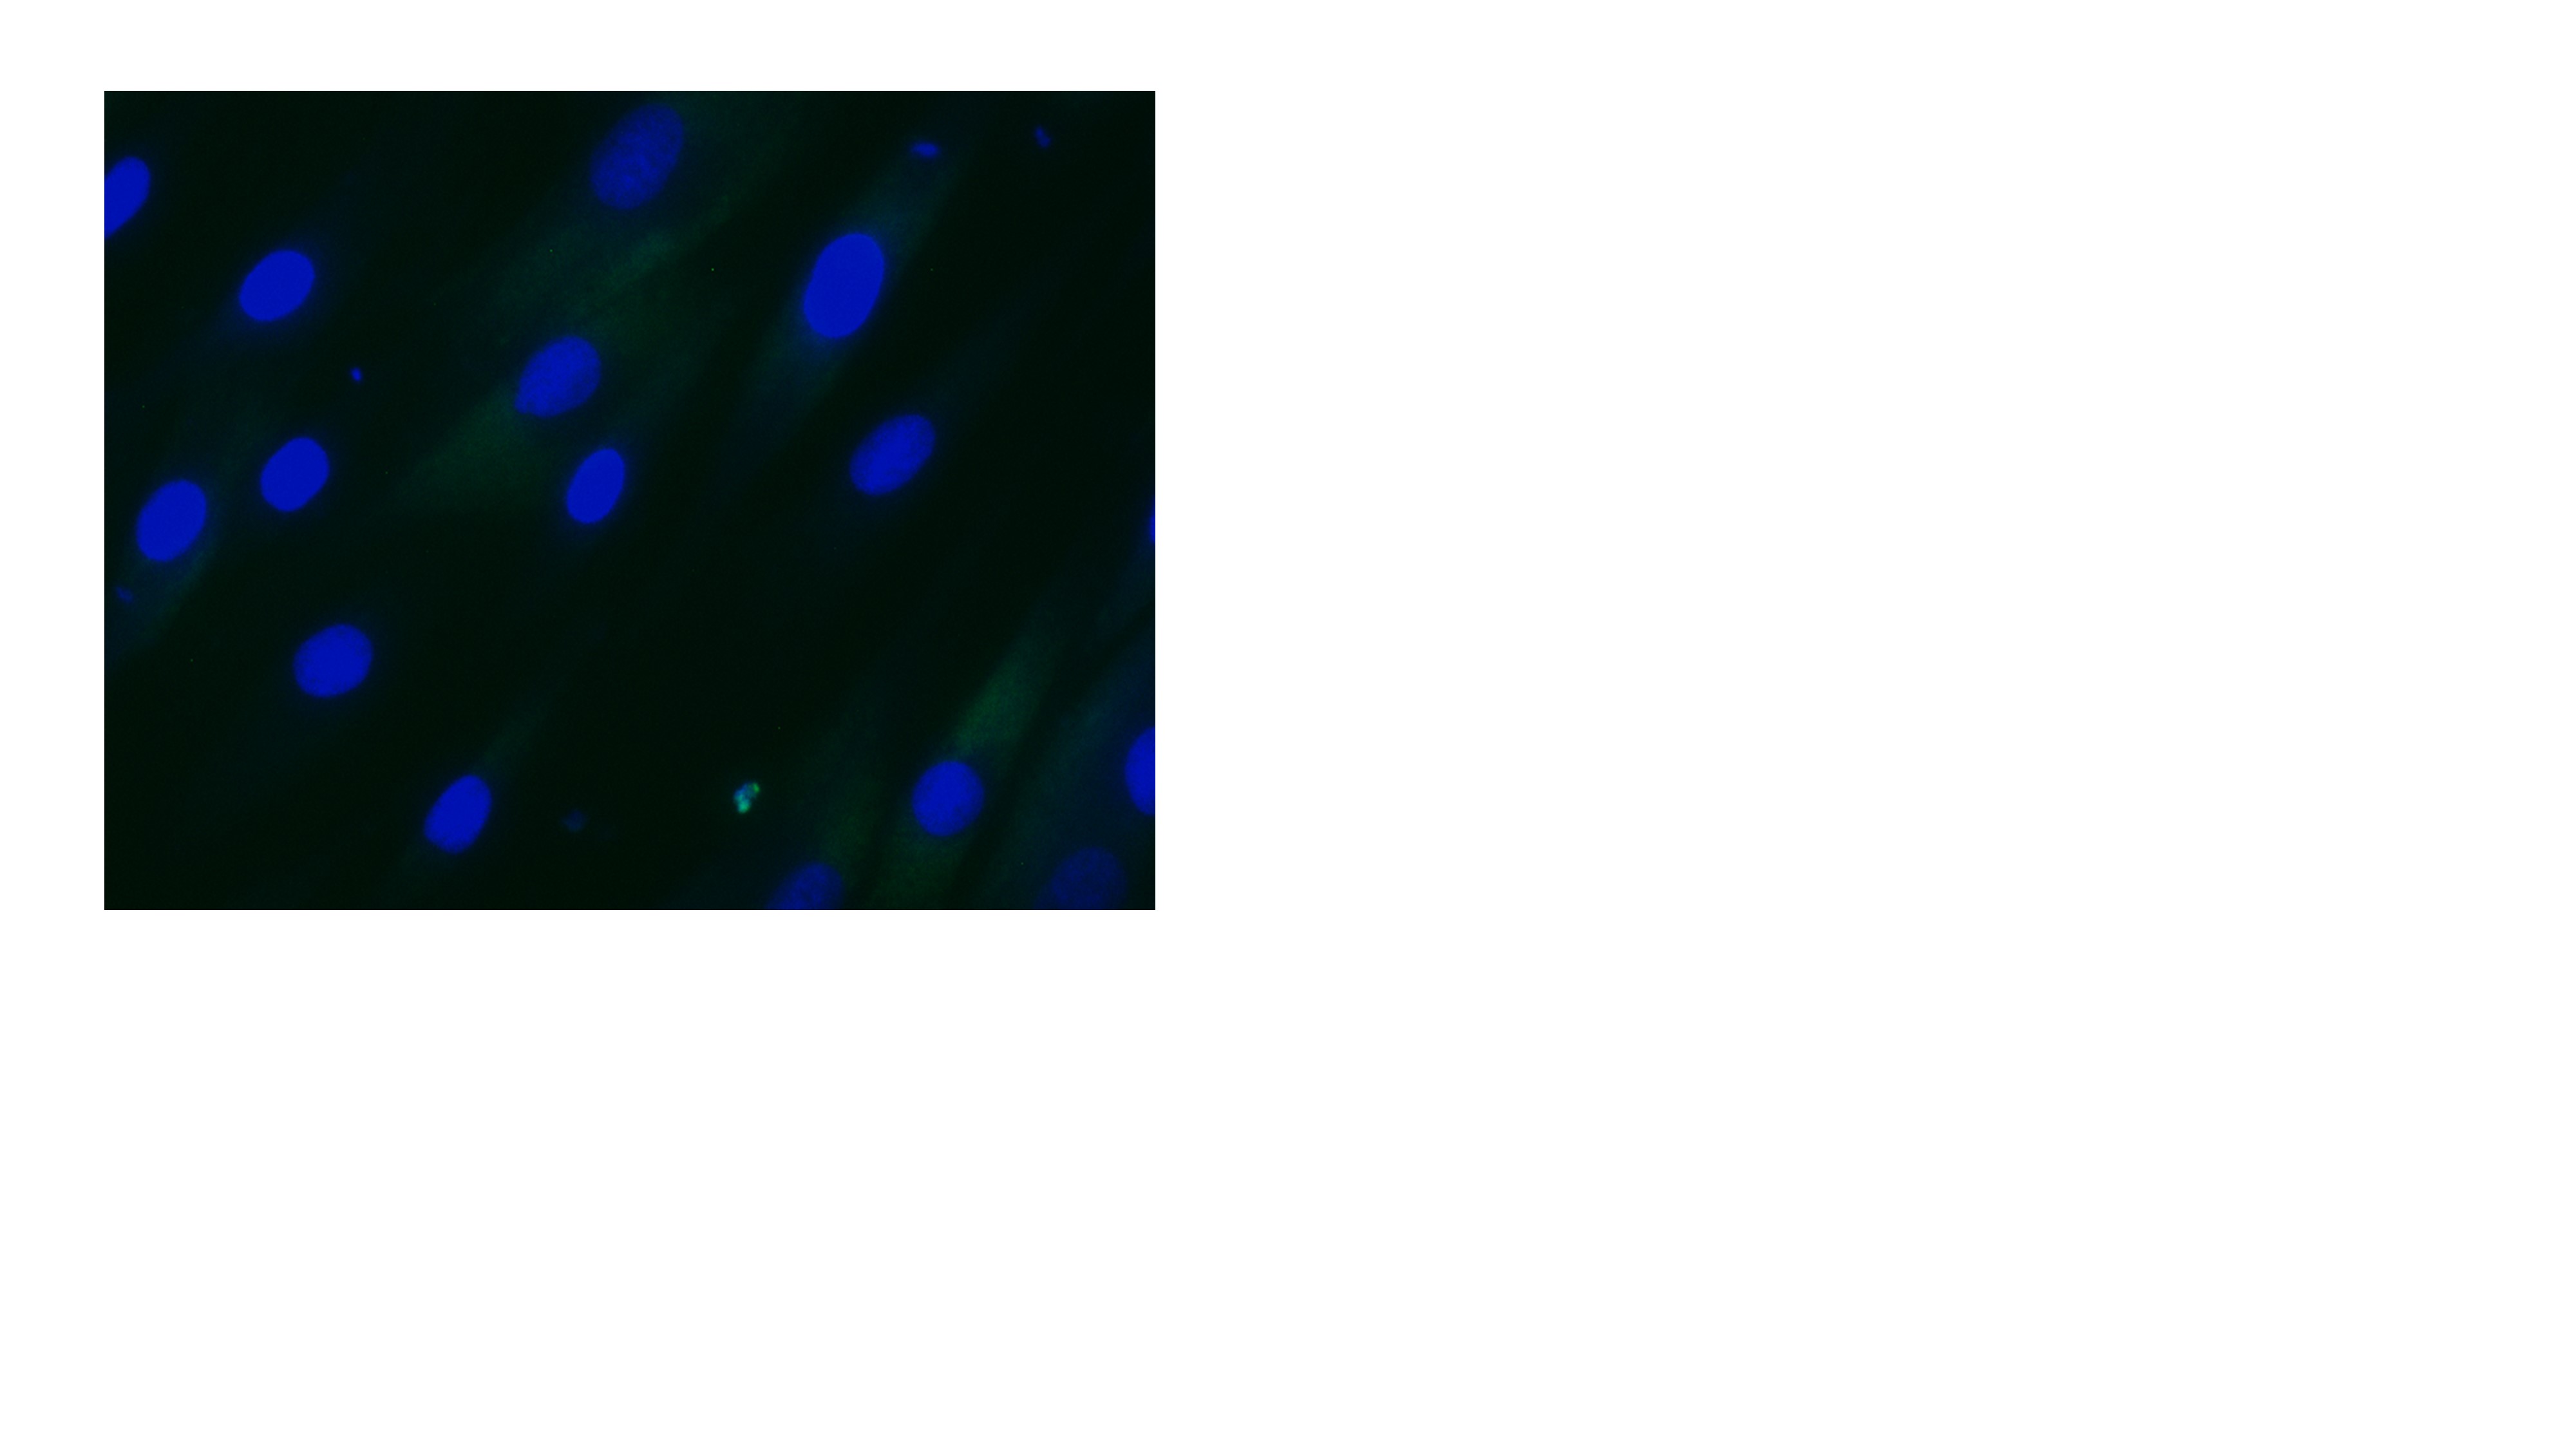

Images show DM1 cells untreated:

David Brook, Professor of Human Molecular Genetics in the School of Life Sciences, is the lead researcher on the study, He said: "Through our research we now understand a key molecular component in the pathway of the condition and that's a target for us to try to inhibit this particular CDK12 protein which will then have beneficial effects in terms of developing a treatment.

"Transcription is the process by which RNA is made from DNA and this can require CDK12. When the repeat sequence is transcribed, it makes the faulty expansion RNA – but we think that the myotonic dystrophy patients' cells struggle to make the faulty RNA and they increase their levels of CDK12 to keep ploughing through the expansion sequence and make more of this RNA because the cell doesn't know this is toxic.

"What we've found is that our inhibitors affect the function of CDK12 and so prevent the transcription of the faulty RNA which offers a possible route to a treatment of the condition.